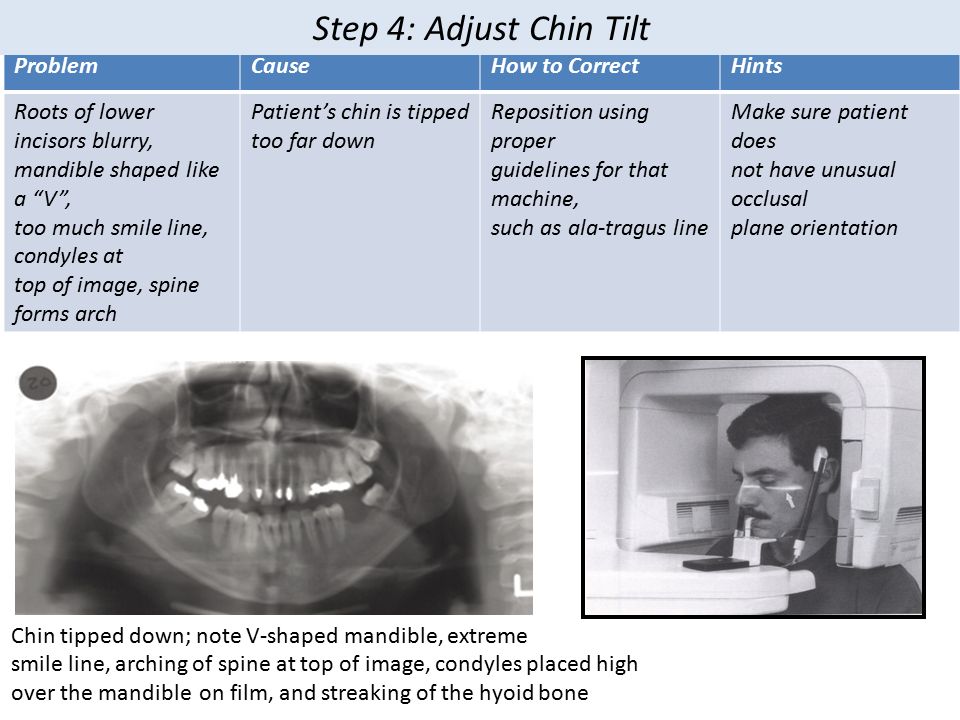

Tragus of the ear must be aligned with the plastic guides ala tragus line should be 50 from level positioning the patient position the patient panoramic lead apron must be used position apron high in front to protect the thyroid apron should be lower in back to expose the neck. Discussion most panoramic x ray machines use the ala tragus line for patient positioning whereas a few use the orbito meatal line. Ala tragus line is one of the common extra oral soft tissue land mark utilized in dental clinics for occlusal plane orientation. Here the occlusal plane should be mildly curved upward to make a smile like line.

The angle between this line and the horizontal plane is 3on the panorex and 4on the. Focal trough layer that area between the x ray source and the image receptor that will be imaged distinctly on the panoramic. In other words the ala of the nose should be slightly inferior to the height of the tragus. These zones are as follows.

Important in determining the correct position of the patient s head. Exposure was 80 to 90 kv at 10 ma for 1 5 to 2 seconds in accordance with the subject s physical. The panorex i s. To achieve the correct vertical angulation the head must be positioned upright and symmetrical with the ala of the nose just inferior to the height of the tragus.